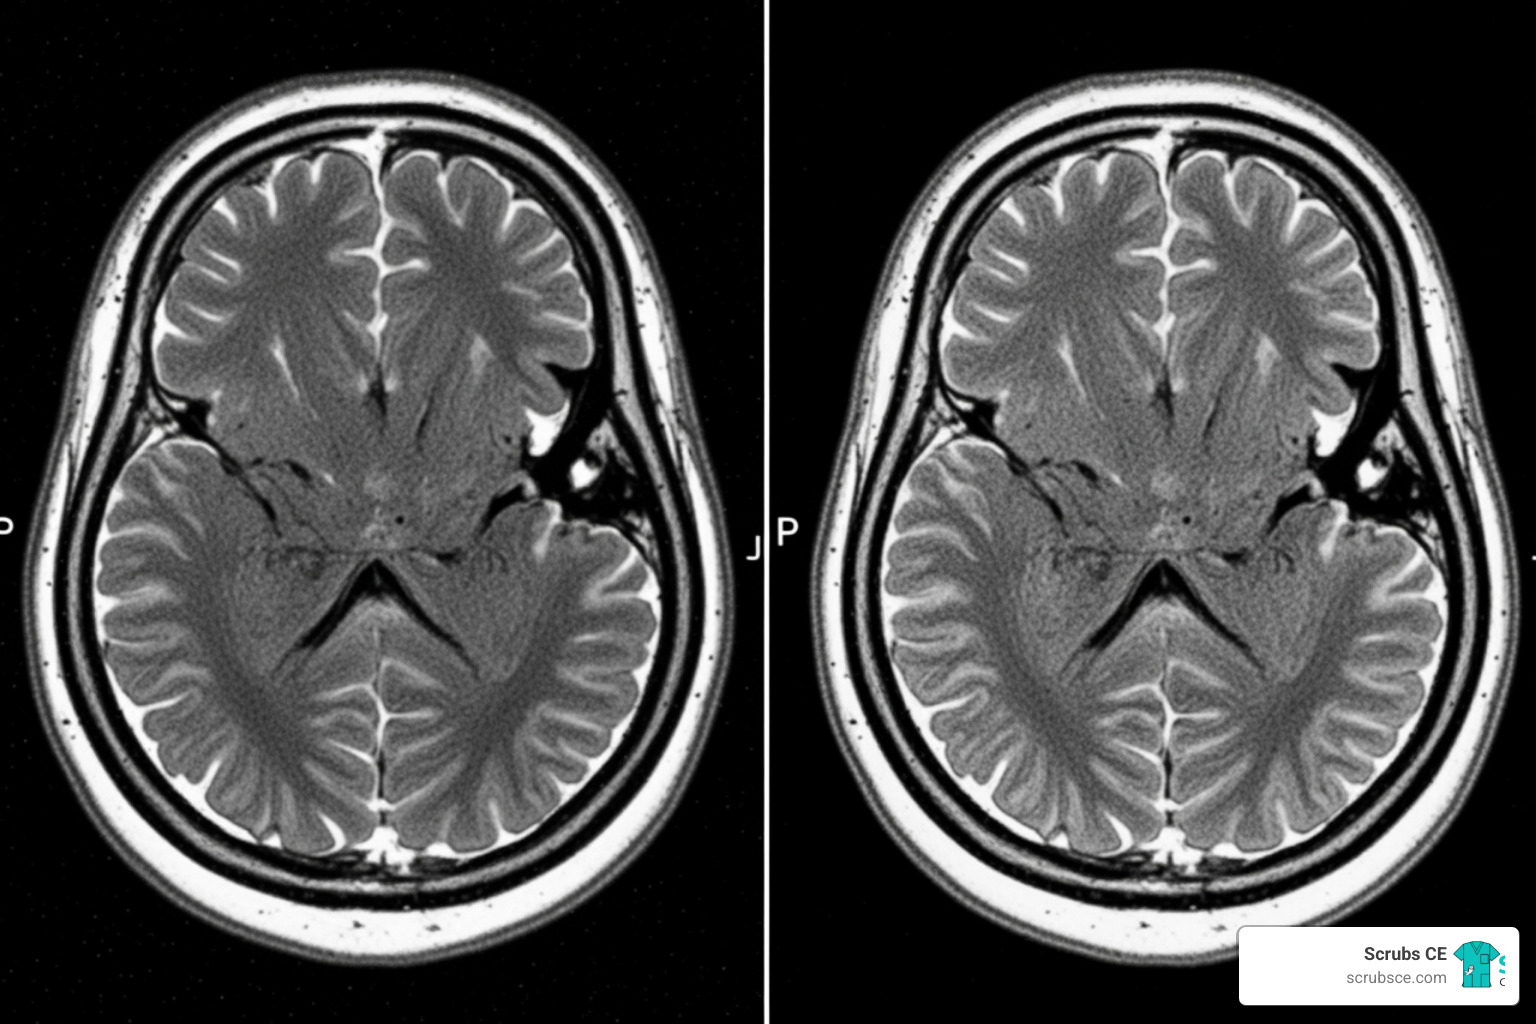

The star of the show right now is Deep Resolve, an AI-powered image reconstruction technology. By using deep learning algorithms, this system can take “noisy” raw data and turn it into crystal-clear images. Think of it like a high-end noise-canceling headphone, but for your pixels.

The impact on scan times is staggering. On average, Deep Resolve shortens exams by 7 to 10 minutes. For complex brain scans, we are seeing time reductions of up to 70%. For a technologist, this means fewer “Can you hold still for just five more minutes?” requests. For the patient, it means getting out of that tube much faster.

Deep Learning in Clinical Practice

We aren’t just speculating about these benefits; we have the data to prove they work in the real world. Take NHS Fife, for example. Since adopting Deep Resolve technology, they have seen a total transformation in their diagnostic capacity.

In just the first six months of implementation, NHS Fife was able to perform 1,900 extra appointments. By reducing the average scan time from 30 minutes to less than 24 minutes (a 20% improvement), they slashed their patient waiting lists from six weeks down to just three or four weeks. This is a massive win for public health, proving that AI can help healthcare systems do more with the same amount of equipment.

Improving Patient Outcomes in Radiology

Beyond the numbers, New MRI technology is improving the actual quality of care. Higher signal-to-noise ratios mean that radiologists can see smaller lesions with greater clinical confidence. Furthermore, motion-robust imaging sequences powered by AI allow us to get diagnostic-quality images even from patients who are in pain or have difficulty staying still.